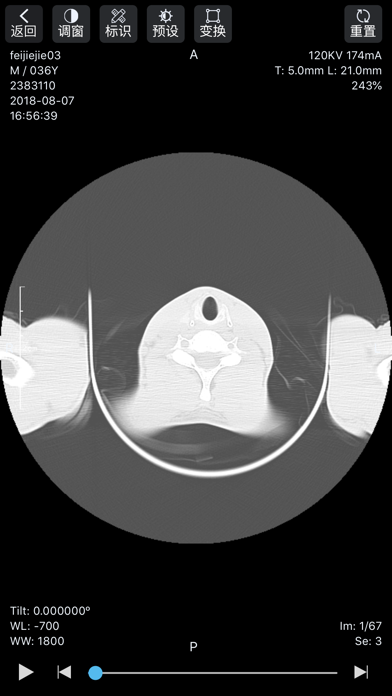

飞图影像App是飞图影像云平台的移动端应用,医生通过此应用,可实现以下功能: - 移动办公——随时随地调阅影像数据,无论在院内还是院外,都可阅片、写报告; - 医疗协作——疑难病例发起协助请求,请求上级医生或专家予以协助,远程诊断; - 交流研讨——与其他医生分享病例,进行专业研讨和学术交流,提升专业技能。 技术特性: - 原始数据,高清影像——DICOM格式,信息细节全保存,精度更高; - 多项功能,强大实用——可实现WL、测量、角度、CT值、旋转等操作; - 使用简便,快速上手——符合医生使用习惯,无需过多繁琐学习过程; - 秒传秒开,顺滑流畅——领先的GPU计算、影像预加载、影像本地保存等技术,拒绝卡顿、模糊、加载等待时间过长; - 多重措施,确保安全——严格审核,二次验证,防止数据被恶意应用;加密传输,防止信息外泄。1.优化APP性能 2.优化UI 3.新增若干功能

软件截图